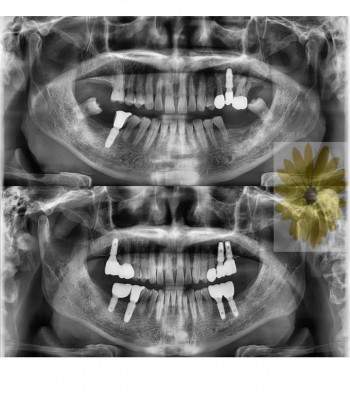

민들레치과 치료 전후사례